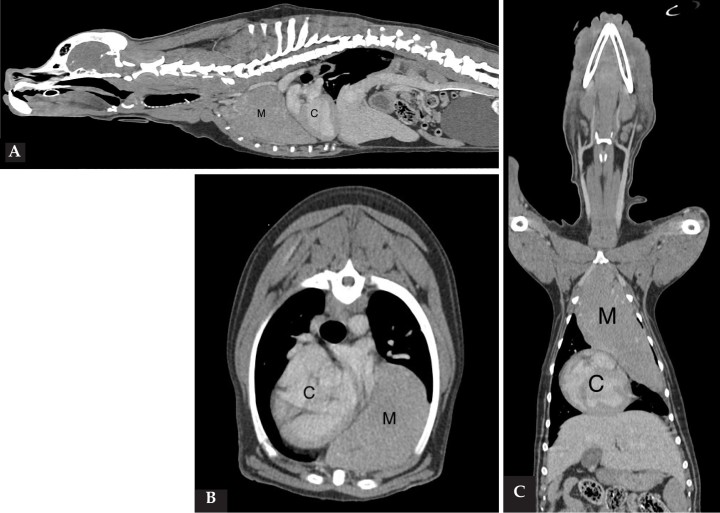

Imágenes de TC postcontraste en ventana de tejido blando de la masa en mediastino craneal, extendiéndose hacia el lado izquierdo del tórax. (A) Plano sagital. (B) Plano axial. (C) Plano coronal. Nótese el corazón desplazado en dirección caudal y hacia el lado derecho. M: masa; C: corazón.

1. Tomografia computarizada (TC): se realizó un estudio de cuerpo completo, incluyendo imágenes pre y postcontraste intravenoso, procesadas con algoritmo de tejidos blandos y de pulmón, con espesor de cortes de 1 mm, donde se evidenció la presencia de una masa en el mediastino craneal, extendiéndose hacia el hemitórax izquierdo, con unas medidas de 16,6 cm de largo por 7 cm de ancho y 8,7 cm de alto. La lesión presentaba márgenes bien definidos, atenuación de tejidos blandos, realce leve y homogéneo. La lesión causaba un desplazamiento dorsolateral hacia la derecha de los principales vasos del mediastino craneal, y compresión moderada/severa de la vena cava craneal. La lesión se encontraba en contacto con el aspecto craneolateral izquierdo del corazón, que aparecía desplazado caudalmente y hacia el lado derecho por la masa mediastínica. Era también visible la retracción de los lóbulos pulmonares craneales, más evidente en el lado izquierdo, debido a la expansión de la lesión mediastínica (Fig. 2).